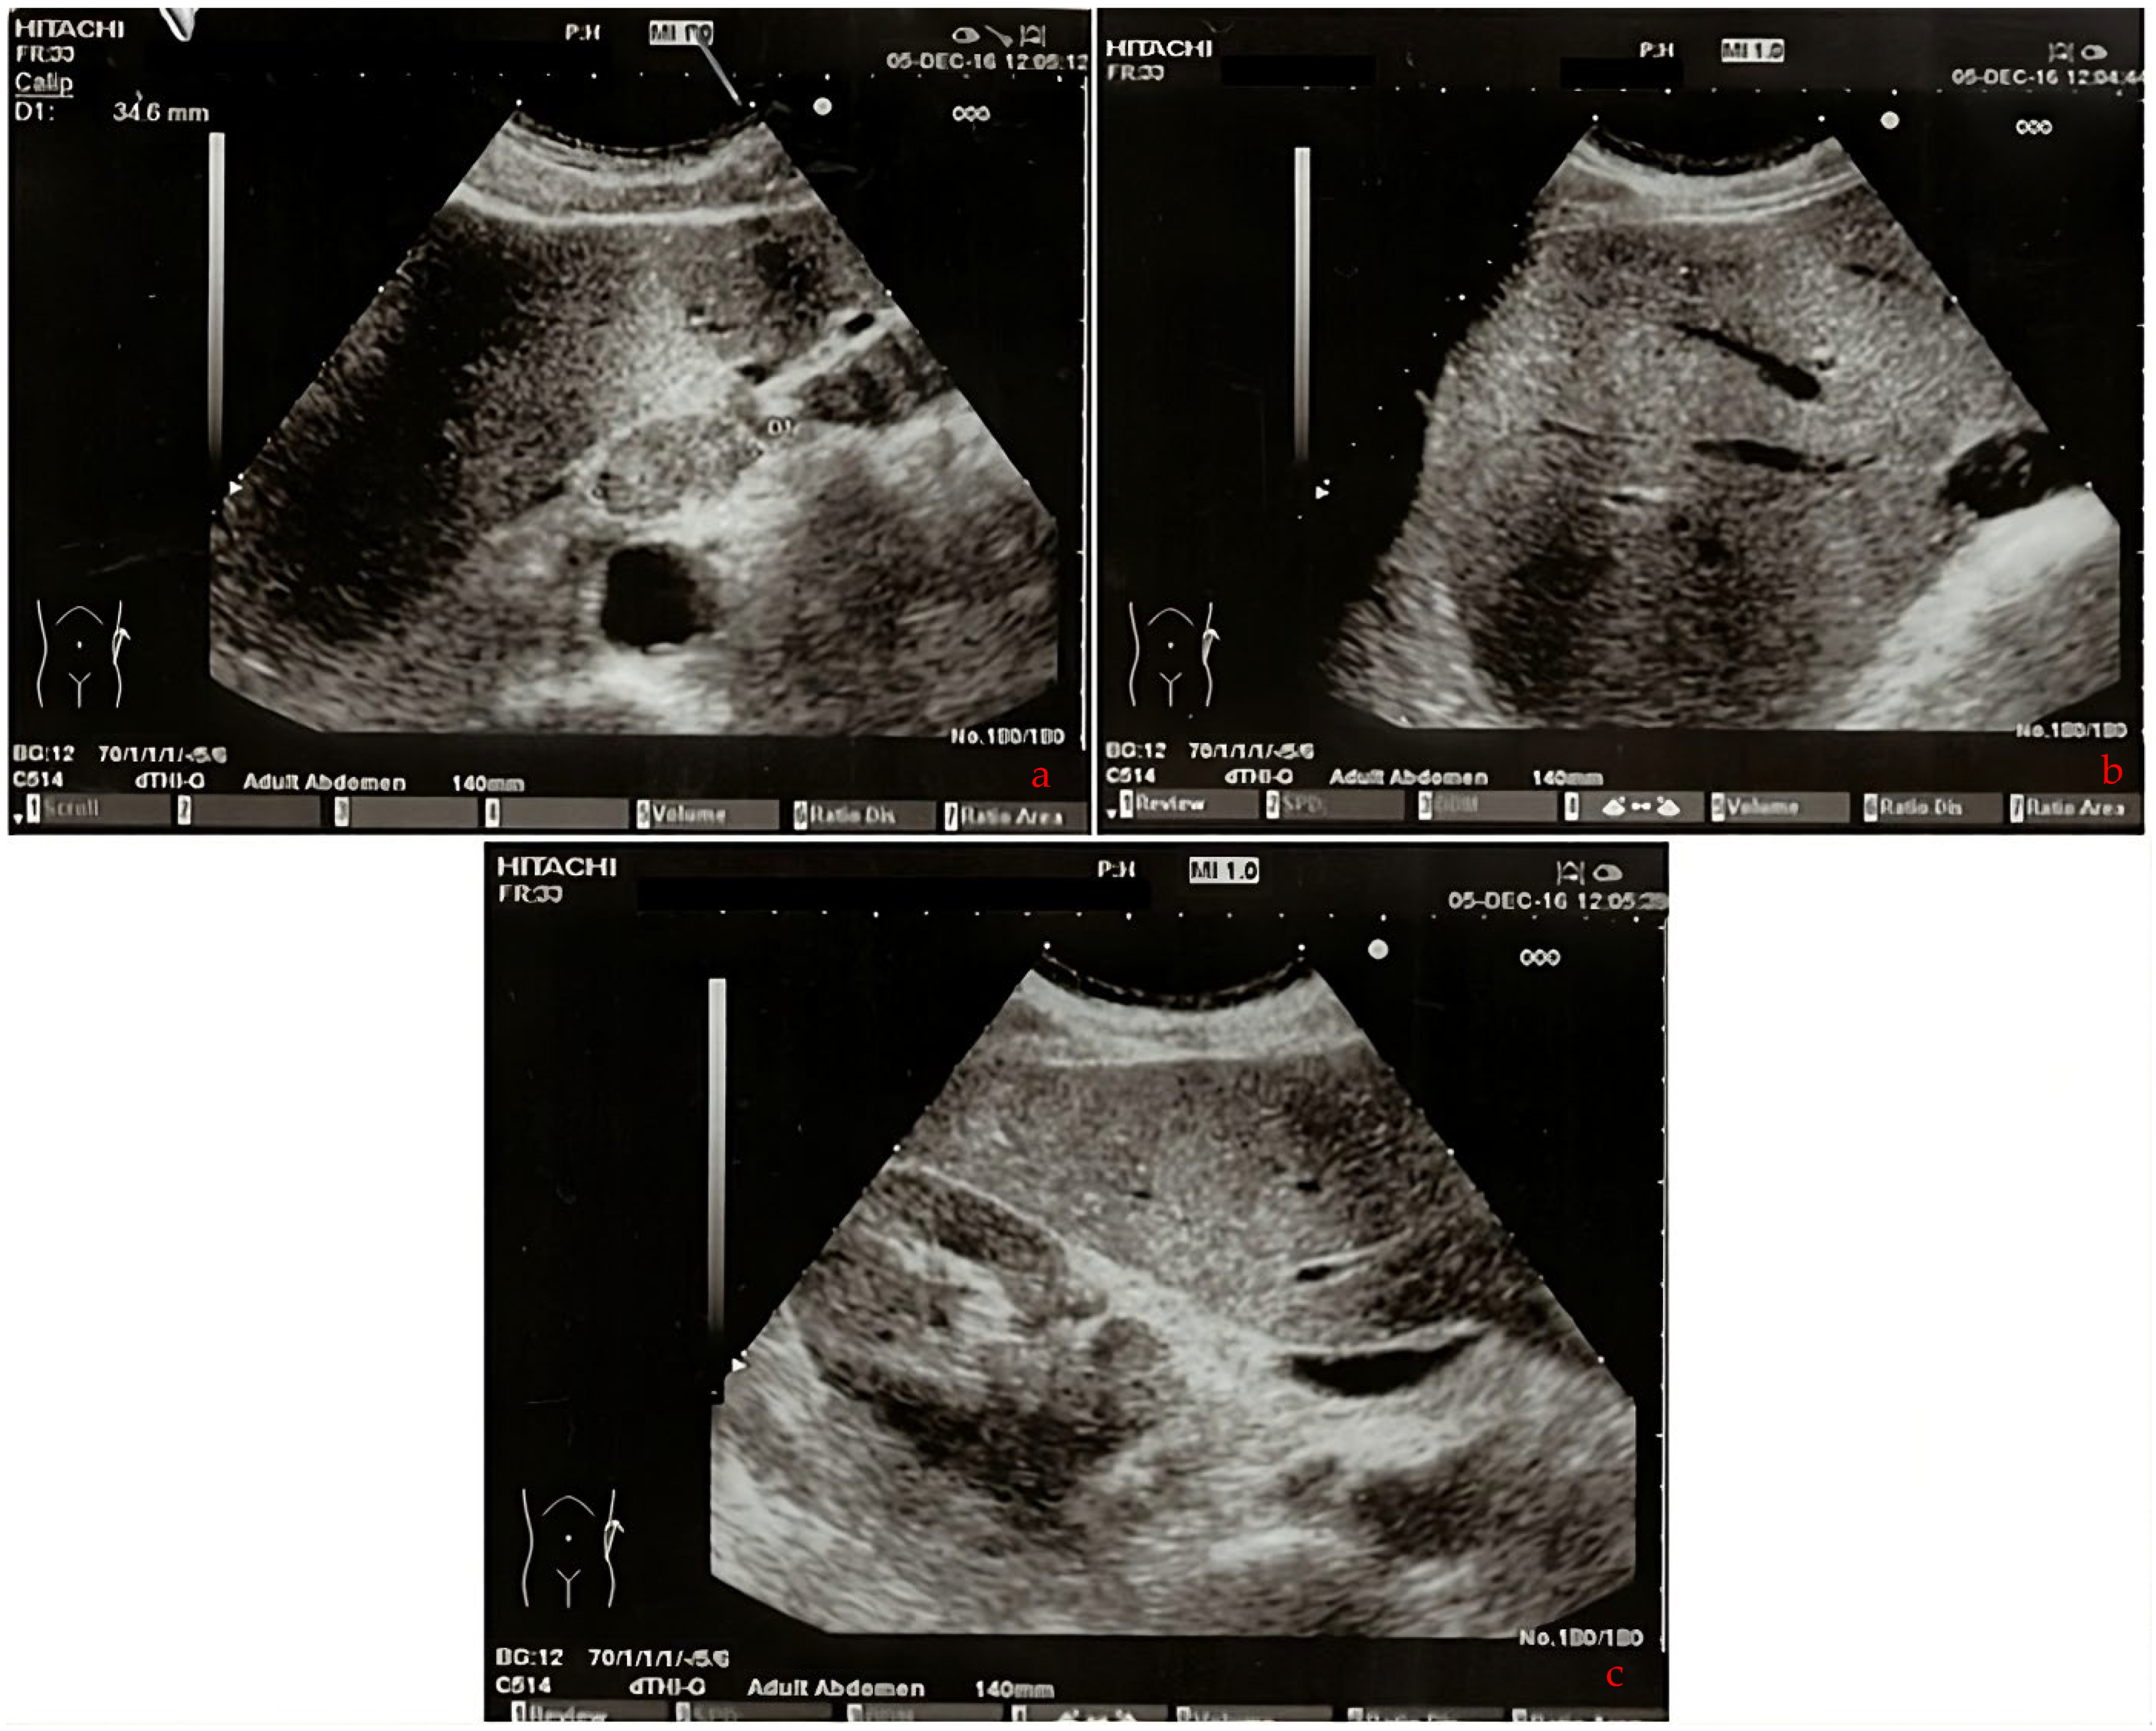

| 2016 | Patient presentation Diagnosis Abdominal ultrasound Total body CT scan | Worsening non-productive night cough, no dyspnea. Metastatic lung cancer. Presence of malignant lymph nodes near the hepatic hilum. Solid nodular- like expansive process in the right upper lobe of the lung and multiple lymphadenopathies in the mediastinum and abdomen. |